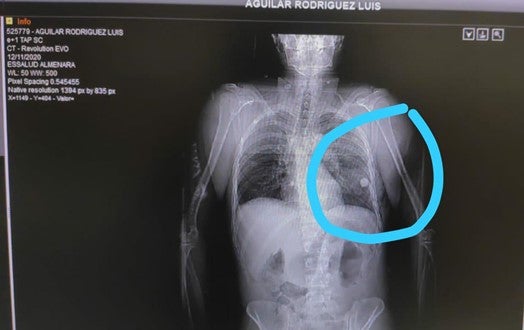

X-ray showing a marble lodged in Luis Aguilar Rodriguez’s lung. Photo courtesy of Luis Aguilar Rodriguez’s family.